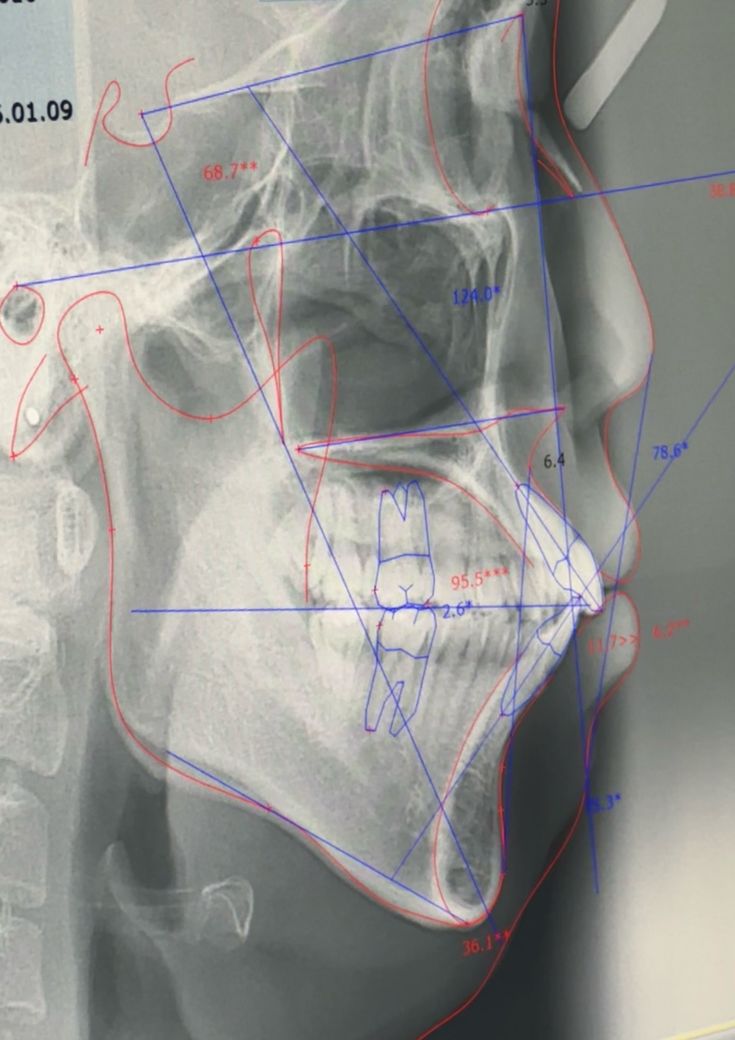

어금니나 견치 교합은 상대적으로 안정된 상태인 반면, 앞니 돌출이 심한데 이런 경우 앞니를 집어넣기 위한 공간이 부족해 발치교정이 우선고려될 것 같습니다.

담단 비발치, 발치 교정에 대해서는 정확한 진단 계측이 필요합니다. 이정도 사진 가지곤 뭘 할 수 있는게 없습니다.